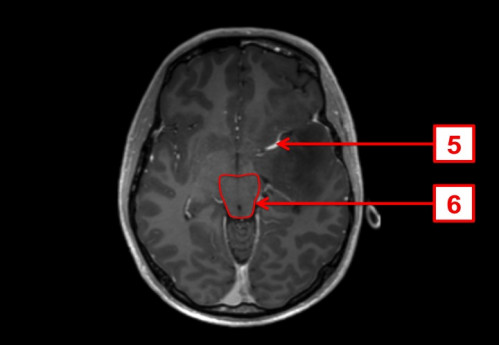

ICD: C71.9

ICD: R47.0

ICD: R51

23-jähriger Mann. Bereits seit Jahren plagen ihn Kopfschmerzen, die vor allem bei körperlicher Belastung auftreten. In den letzten Tagen fühlte er sich zunehmend unwohl, die Kopfschmerzen sind nun auch in Ruhe vorhanden.

Seit gestern Abend erbricht er sich mehrmals, und spricht, als ob er betrunken wäre.